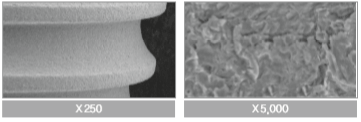

Optimális RBM felület

A felületi finomság 1,5 +-0.2 mikrométer, ami a legtökéletesebb érték az osszeointegrációhoz.